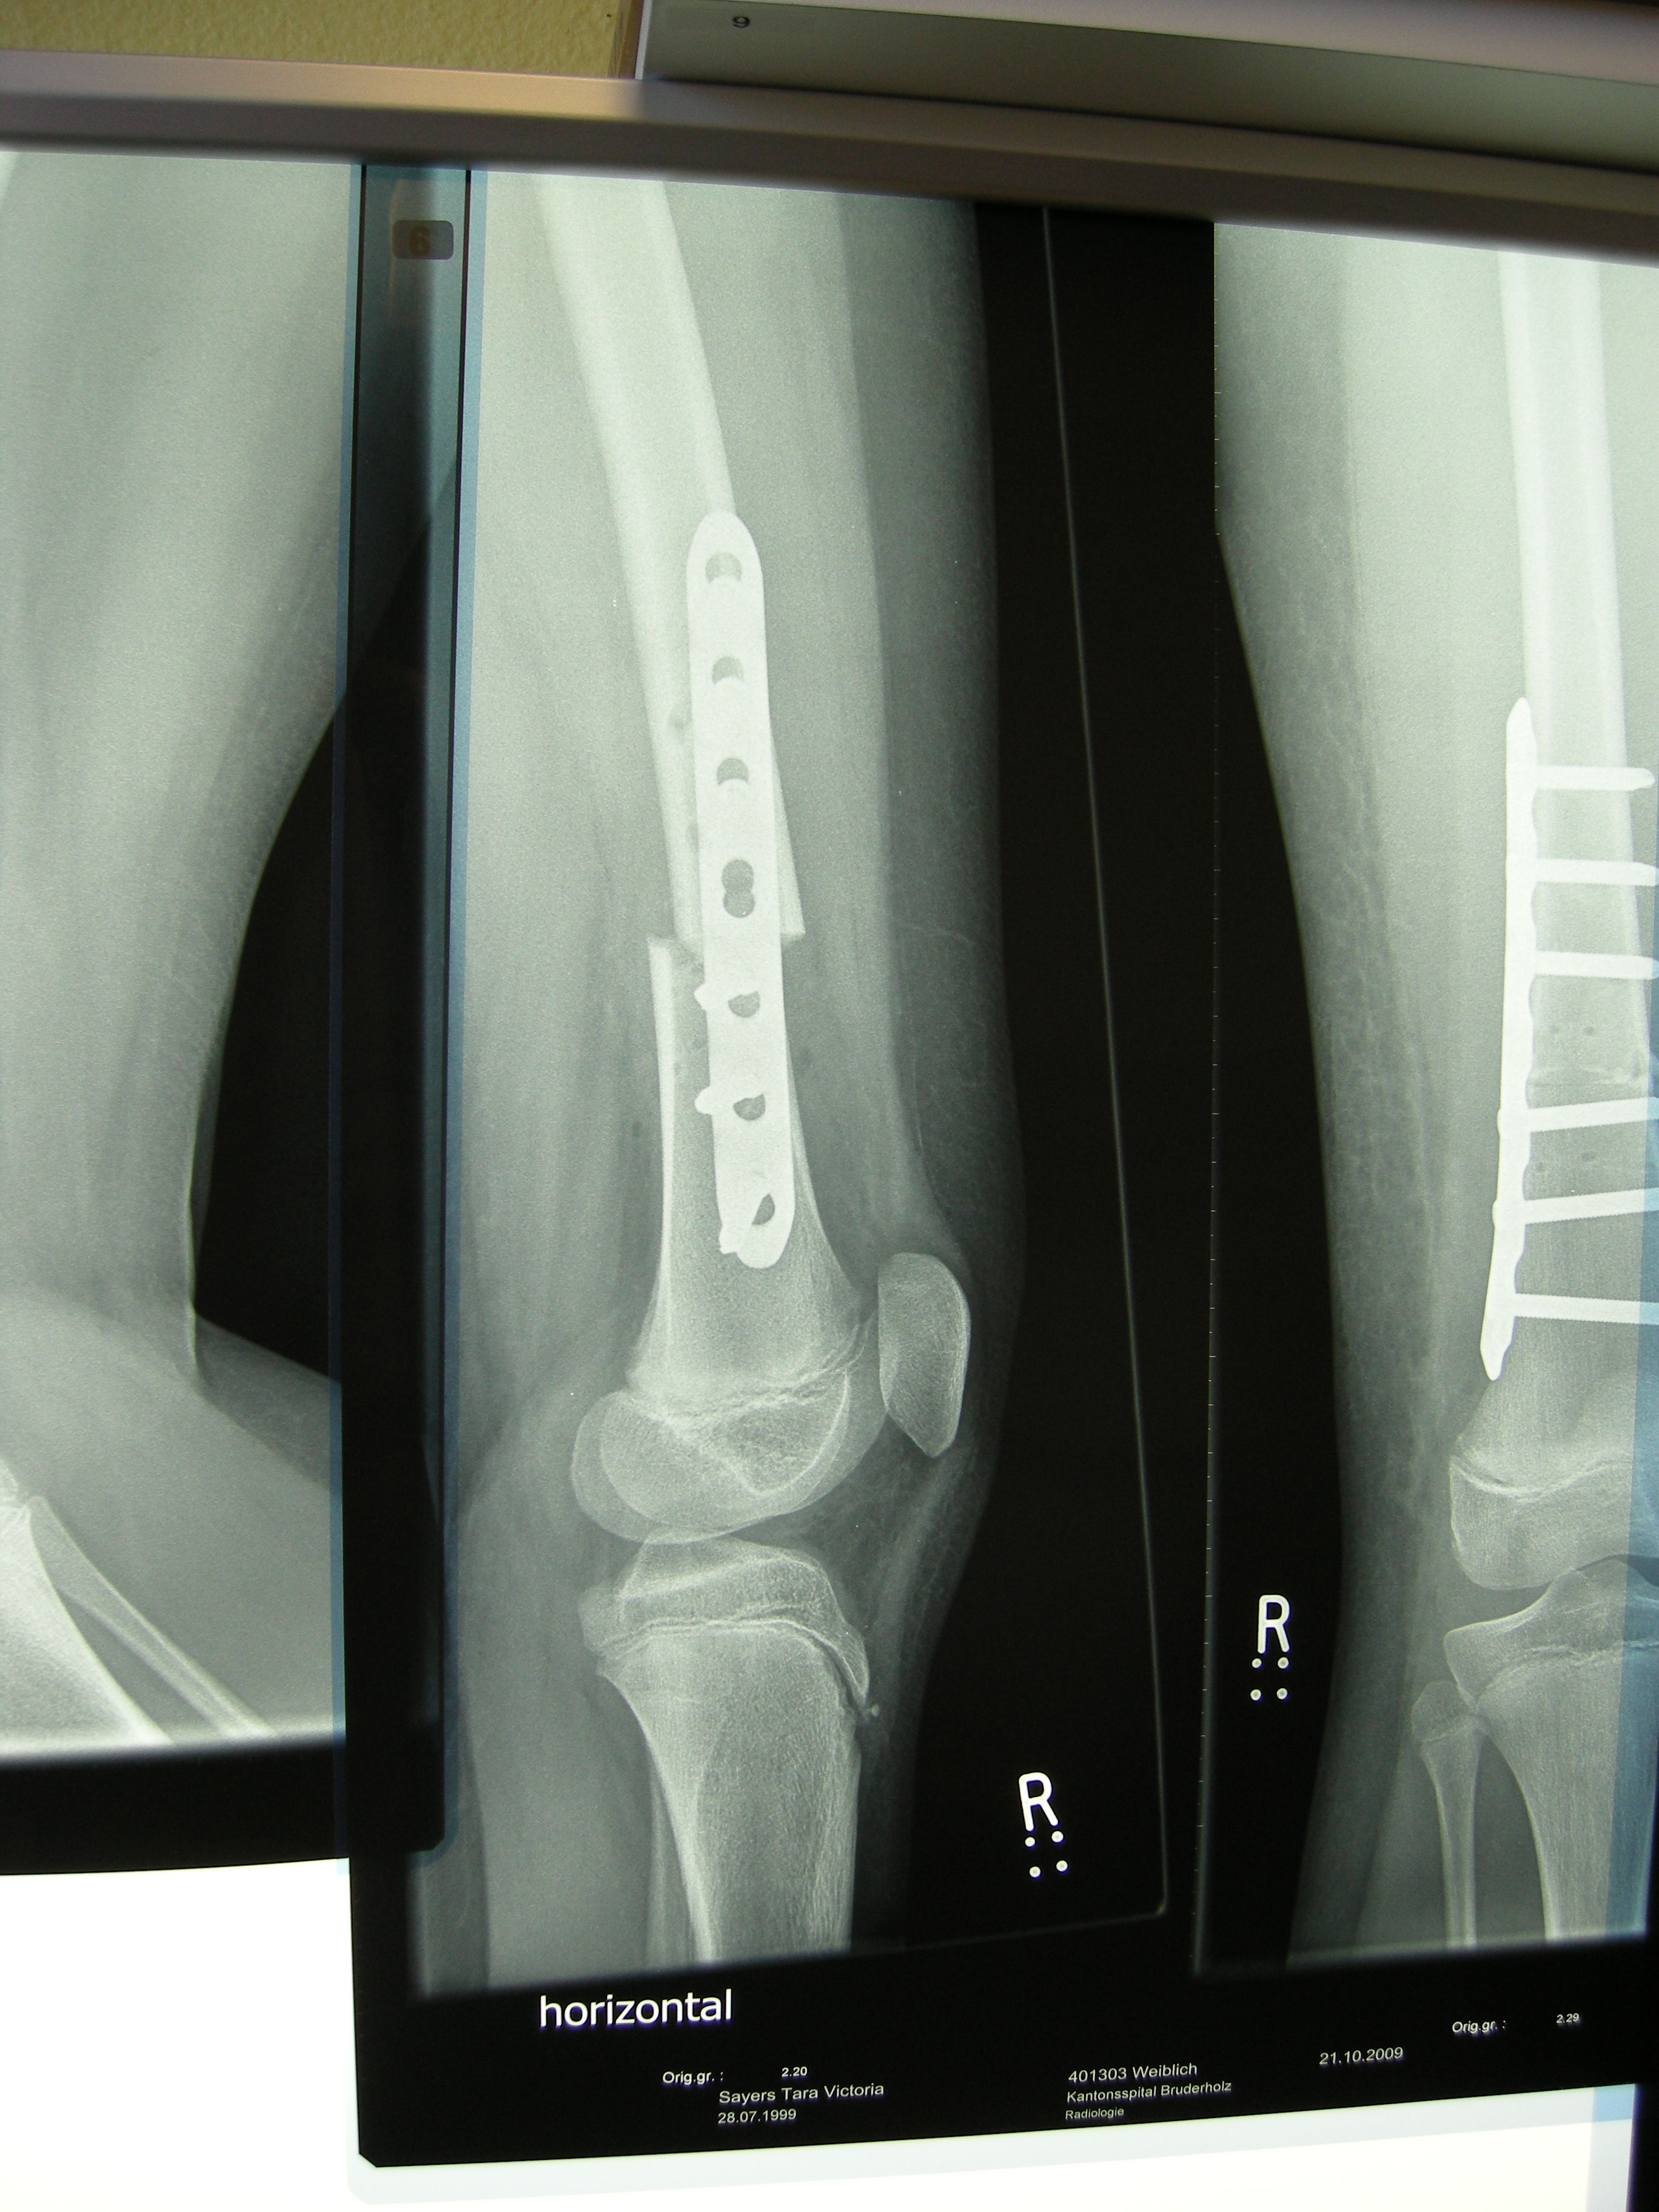

XRays